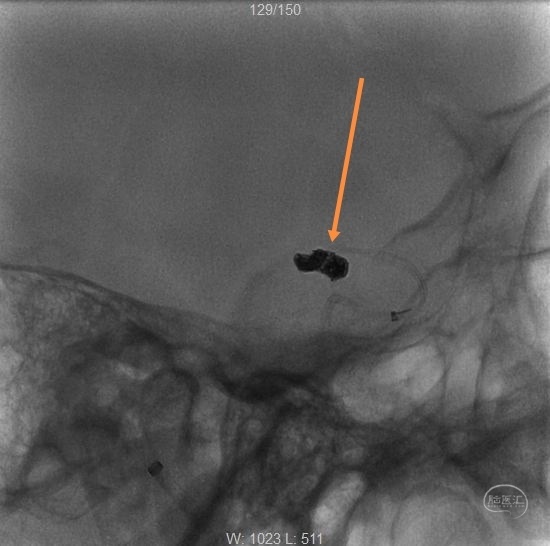

解脱第一枚弹簧圈,经过微导管1,继续填塞,二维Target2-4、APB1.5-4-3D-ES、APB1.5-2- HX-ES、APB1-4-3D-ES各一枚。

撤出微导管1,可见该微导管占据的缝隙,此处仍空虚。

造影

继续经过微导管2植入:APB1-3-3D-ES、二维Target1-2各一枚。